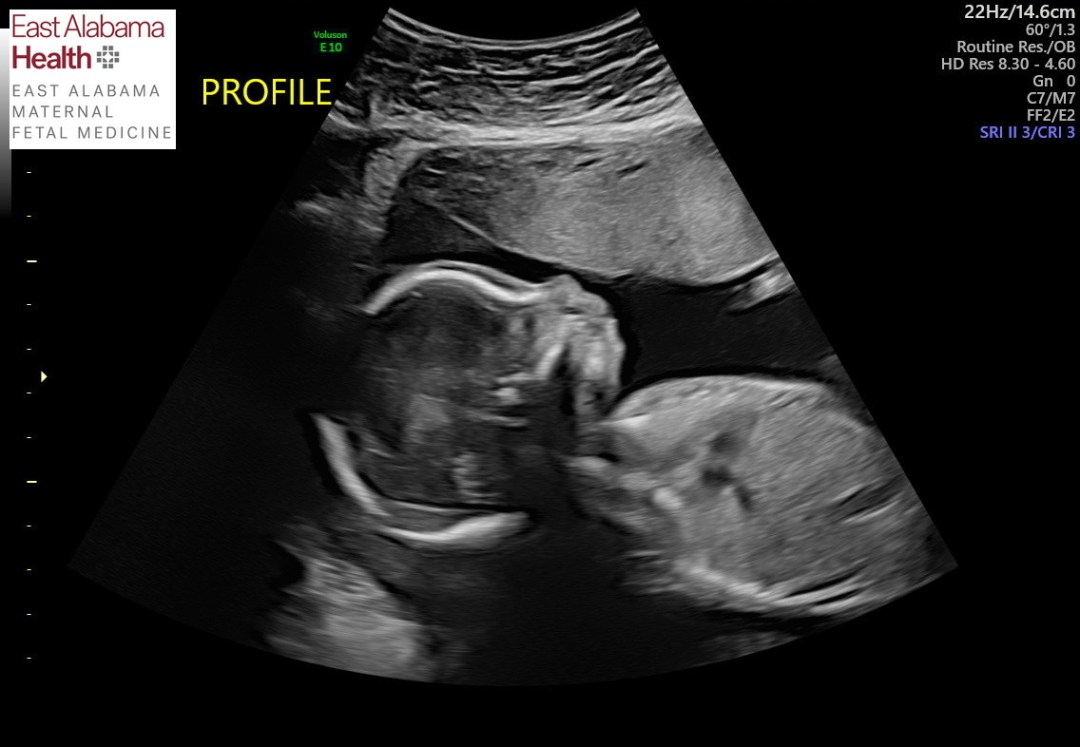

As I gaze at Addie’s ultrasound pictures, I find myself daydreaming about holding her, feeding her, and watching Chet and Daniel love on her. My heart is so full already. Now we need to spend the next 10ish weeks preparing the nursery, preparing Chet, and remembering Ginny as we embrace all we can of this pregnancy in hopes of bringing little sister home.

Addie’s Anatomy Ultrasound

I know too much. Even though the 20 week anatomy ultrasound went really well in Ginny’s pregnancy, I was scared for what we might learn this time around. There is so much that can go wrong. In fact, when things go right, it feels like a miracle. I know so many people whose anatomy scans were their “before and after” moment. That’s the moment that divides the “before” – when things were all good and the “after” – when they are faced with hardship. I hoped and prayed that this scan would not be our 2nd “before and after” moment (our 1st was when we found out Ginny had died).

I didn’t want to be scared or to have those thoughts. I wanted what we had with Ginny’s anatomy scan; I wanted to just enjoy seeing my little girl wiggle and see her sweet features for the first time. But I have to face the reality that that isn’t my story anymore. All the positive thinking in the world can’t make me unlearn what I now know, and it can’t magically erase trauma. I’ve lost my naivety. And that’s okay. It’s hard, but it’s okay.

I rescheduled the ultrasound from Wednesday afternoon to Monday morning. I wouldn’t be able to wait and wanted to get it over with as early in the week as possible. I was eager to see Addie again. I hadn’t had an ultrasound since week 9. I was excited to get pictures and watch Daniel see her move on screen. But mostly I wanted relief in knowing she was developing and growing. Daniel’s parents had been in the room with both Ginny and Chet’s anatomy scans. We wanted to make it 3 out of 3, so they planned their visit here to coincide with the appointment. Daniel’s dad stayed home with Chet while his mom came along to the ultrasound. Unfortunately when we arrived, we were informed she may not be able to come in. The sonographer wanted minimal distractions. This was a high risk ultrasound with very precise measurements and sometimes tricky angles. There were many pictures and measurements required in a limited time. We were reminded that this was not a scan for fun pictures. What was already anticipated to be a really tense appointment felt even more so.

Ultrasounds can be triggering since it was in an ultrasound that we were given the news that Ginny died. I knew I needed to let the sonographer know from the very beginning that we had a stillbirth so she may have more understanding if things get hard. It is extremely challenging to meet someone new, already be so anxious, be in the same cold, triggering environment you were in when you got the worst news, and speak out loud, “I should tell you that we had a stillborn daughter at 35 weeks.” All that while trying not to break down in tears and being in a very physically vulnerable position on an ultrasound bed with pants off and stomach bare. She told me she already knew of my stillbirth from my chart and then said some sympathetic words.

She proceeded to start taking measurements. Little by little we saw more and more of Addie’s body – her spine, her abdomen, her legs and arms, her head. We saw her little movements. It was a blessing to see her. But with each angle we saw, I was trying to analyze if everything looked healthy. I was trying to read the screen as well as the body language of the sonographer. I’m unqualified, but she knows what she’s seeing. She just can’t say – good or bad. She kept going back to the heart. In Chet’s anatomy scan I remember so clearly seeing 4 chambers of his heart. I remember feeling relieved because it looked so normal. Now with Addie, I was only seeing 3 chambers. The sonographer said she needed Addie to move positions so she could get a better angle. We tried poking her, turning to my side, even getting up and moving around. Addie wouldn’t cooperate. The sonographer gave us the okay to invite Daniel’s mom back as we tried a few more times. No luck. We would likely have to come back for another ultrasound. My mind was going through all the scenarios. Maybe if we are lucky and she lives, she will need heart surgery right away. Maybe she will eventually need a heart transplant. I just want her to live.

As we waited to meet with the Maternal Fetal Medicine (MFM) doctor who would give us the results, Daniel and I spoke about how we really wished this was more fun. We forgot how nerve wracking the whole process was. We lamented how our minds go to the worst outcomes. I’m glad his mom was there for support.

The MFM came in and said everything she saw looked really good, but she didn’t have a good picture of the heart. She asked us to follow her into another ultrasound room so she could take a look herself. I laid back down, and she was able to see what she needed to. Everything looked great! Her heart looked good! I was relieved. I’m so grateful for our MFM; she has listened to my concerns and she took the time to do the ultrasound herself. I’m so glad I didn’t have to come back on another day and wait anxiously not knowing if Addie was healthy.

As relieved as I was that we got a good report, I am not as relieved as I feel I should be. As I mentioned before, Ginny’s anatomy scan also looked great. We are all too aware that things can go wrong in the 2nd half of pregnancy. I am still trusting God with our little girl no matter what. She is His, and His will be done. I really really hope to get to bring her home in September. Everything so far is looking good for that to happen, but I know I won’t feel safe until she’s in my arms. I can’t wait for that day!